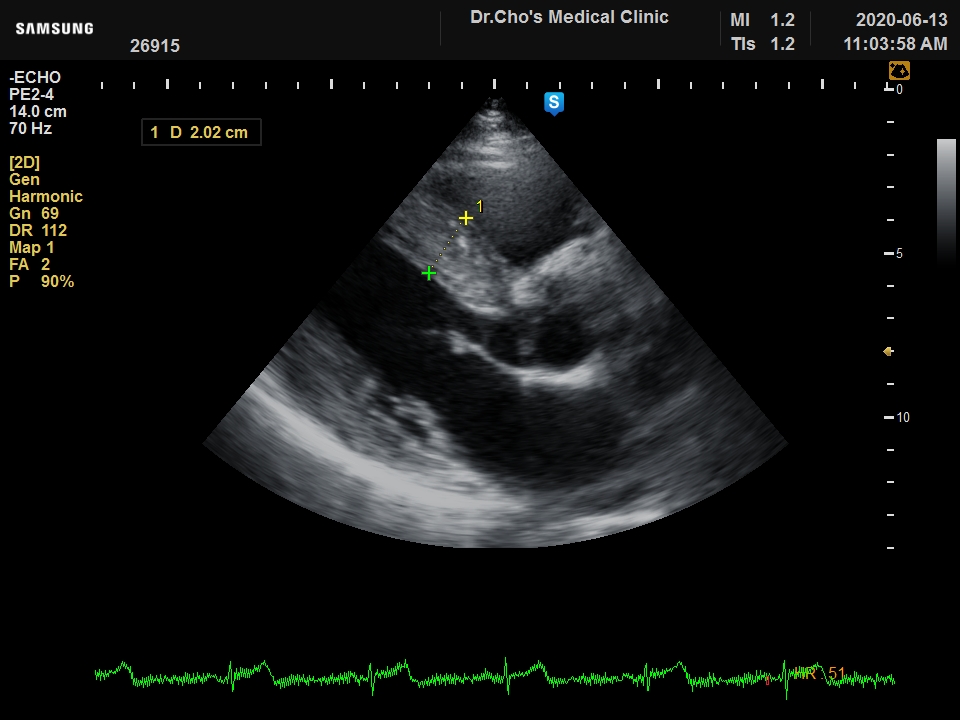

ÃÊÀ½ÆÄ°¶·¯¸®

¿ì½É½Ç °æ...

ºñÈļº ½É...

È®À强 ½É...